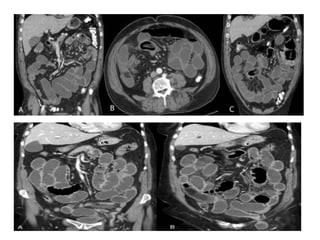

El estudio de Tomografía por

Computadora tiene una sensibilidad

del 80 al9 0 %

HALLAZGOS:

 Dilatación proximalde intestino

 Descompresión distalde intestino

 Contraste intraluminalque no pasa

más allá de la obstrucción

 Intestino distal con poco gas

•La presencia de asa intestinal en

forma de U o de C indica obstrucción

de asa cerrada

•Neumatosis intestinal

,gas en la

vena porta,opacidad mesentérica y

captación deficiente del contraste

intravenoso en la pared hace pensar

en estrangulamiento

El estudio deTomografía por Computadora tiene una sensibilidad del 80 al9 0 % HALLAZGOS:  Dilatación proximalde intestino  Descompresión distalde intestino  Contraste intraluminalque no pasa más allá de la obstrucción  Intestino distal con poco gas

•La presencia deasa intestinal en forma de U o de C indica obstrucción de asa cerrada •Neumatosis intestinal ,gas en la vena porta,opacidad mesentérica y captación deficiente del contraste intravenoso en la pared hace pensar en estrangulamiento